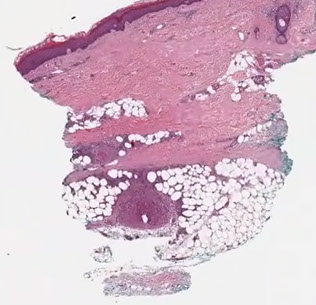

Epithelioid Hemangioma

- aka angiolymphoid hyperplasia with eosinophilia, or histiocytoid hemangioma

Clinically is a multinodular red / purple plaque

- often on temple (craniofacial region)

Micro: multinodular / nodular, large component of round blue cells in background which are lymphs

- clustered vessels with plump eosinophilic endothelial cells

- also lots of eos inbackground

Can be difficult to see vascular spaces, causing concern of angiosarcoma

Epithelioid hemangioma of the penis. A, Sections show a multinodular lesion in the dermis. B, A high-power view demonstrates pleomorphic epithelioid cells with eosinophils. C, The lesional cells are focally positive for pancytokeratin (not shown), and they are diffusely immunoreactive for erythroblast transformation-specific transcription factor (ERG) (D), with a low Ki-67 proliferation index (,5%) and (not shown) retained nuclear integrase interactor 1 (INI1) (hematoxylin-eosin, original magnifications x20 [A] and x200 [B]; original magnification x40 [C and D]).